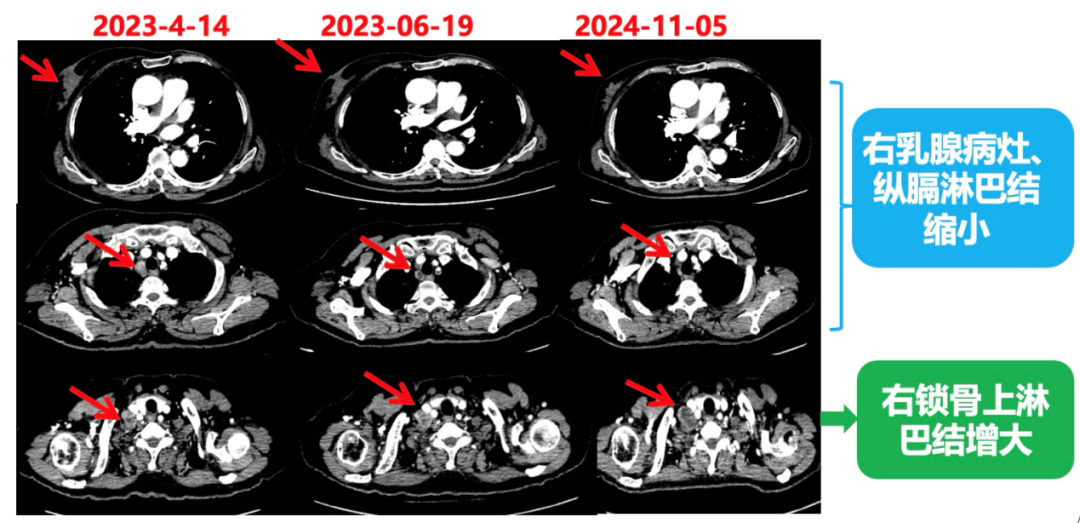

1.右乳外上象限乳腺癌病灶(22*16mm),对比2023-04-14 CT(26*24mm)较前缩小,FDG代谢活跃。右侧腋窝小淋巴结(5mm),较前稍缩小,代谢不活跃。右侧锁骨上区、上纵隔淋巴结转移瘤(24*18mm),现大小同前相仿,代谢活跃(SUV:6.7)。

2024-11-5复查CT:右乳外上象限占位(11mm×9mm),较前明显缩小;上纵隔及右肺门多发淋巴结转移缩小;右锁骨上区淋巴结较前增大。余部位未见肿瘤转移及复发征象。

影像科:CT显示右侧锁骨上区病灶增大主要表现为液化坏死改变,考虑为治疗后改变而非肿瘤进展所致。